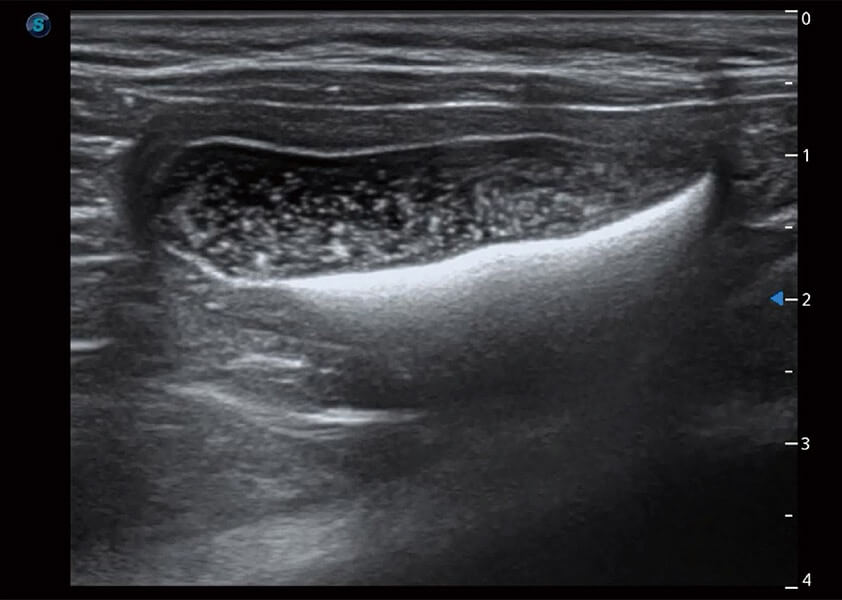

ProPet 60 作為一款高端臺式動物超聲設(shè)備,為動物醫(yī)生的日常診斷提供了一系列貼合動物臨床需求、解決臨床實際問題的高級成像功能。憑借全系列高清探頭,滿足醫(yī)生對腹部、心臟、生殖、淺表、肌骨等成像的所有需求,切實幫助您提升檢查效率,提高診斷信心。

動物是人類最親密的朋友和最值得信賴的伙伴。開立醫(yī)療也一直致力于探索動物專用的超聲影像解決方案。 全新推出的ProPet系列,是開立在動物超聲影像智能化、專業(yè)化、精準(zhǔn)化的一次跨越式革新。動物不能用言語來表述自己的不適,通過超聲影像,ProPet系列搭建了動物醫(yī)生與不同物種溝通的“橋梁”,為動物醫(yī)生注入了“治愈之力”。